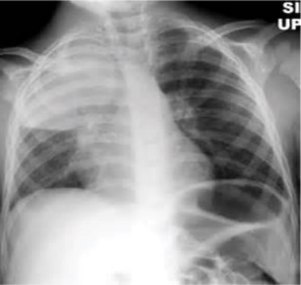

Tuberculosis creates cavities visible in x-rays like this one in the patient's right upper lobe.

A posterior-anterior (PA) chest X-ray is the standard view used; other views (lateral or lordotic) or CT scans may be necessary.[citation needed]

In active pulmonary TB, infiltrates or consolidations and/or cavities are often seen in the upper lungs with or without mediastinal or hilar lymphadenopathy.[1] However, lesions may appear anywhere in the lungs. In HIV and other immunosuppressed persons, any abnormality may indicate TB or the chest X-ray may even appear entirely normal.[1]